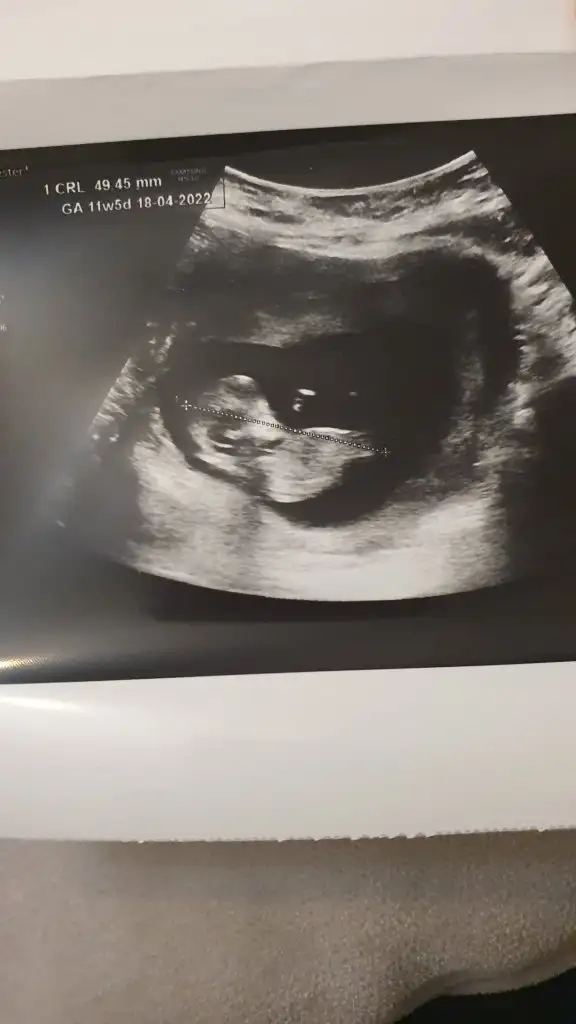

Banada tahmin yapabilir misiniz 12 haftalık

ttecrübeli bayanlar yorum yaparsaniz cok sevinirim...